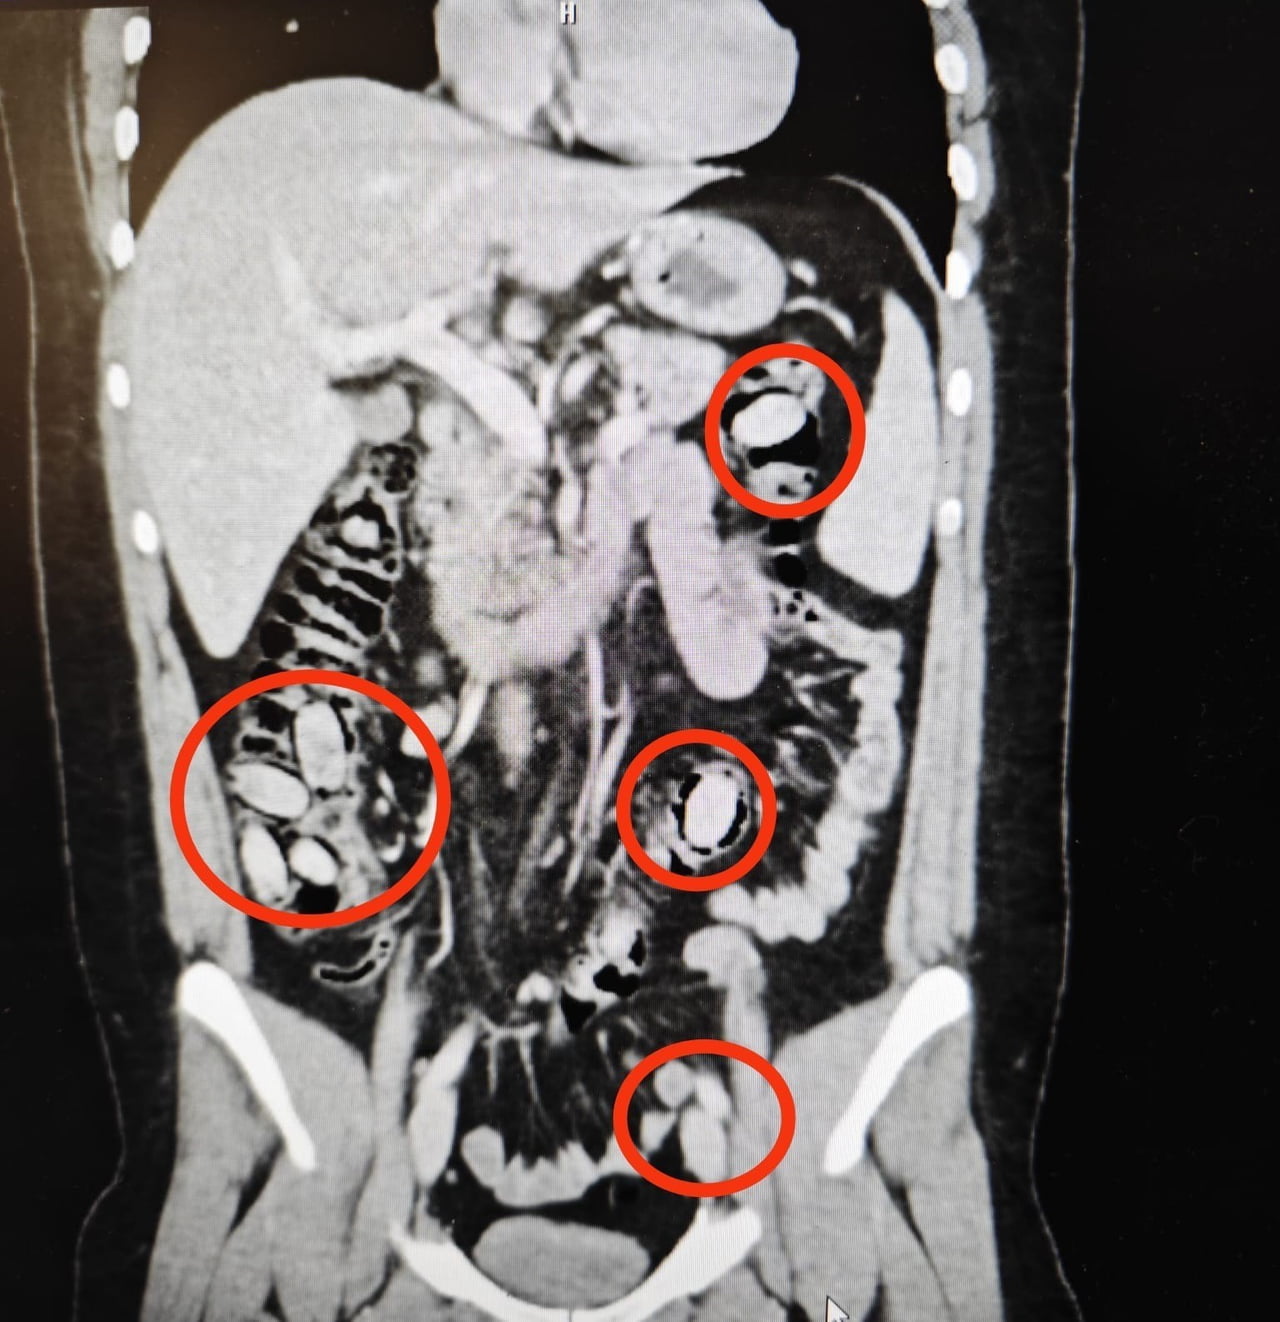

Yurtdışından Eskişehir'e gelen S.A. (25), kent girişindeki kontrol noktasında polis ekiplerinin dikkatini çekti. Şüphe üzerine hastanede yapılan detaylı tetkikler sonucunda şahsın yutmak suretiyle midesinde 44 kapsül metamfetamin taşıdığı tespit edildi.

Sağlık ekiplerinin cerrahi müdahalesiyle kapsüller şahsın bedeninden çıkarıldı. Tedavi sürecinin tamamlanmasının ardından S.A. çıkarıldığı mahkemece tutuklandı.

YURTDIŞINDAN ESKİŞEHİR’E 44 KAPSÜL UYUŞTURUCU MADDEYİ MİDESİNDE SOKMAYA ÇALIŞAN YABANCI UYRUKLU ŞAHIS POLİSİN DİKKATİ SAYESİNDE YAKAYI ELE VERDİ. AMELİYATLA MİDESİNDEN UYUŞTURUCU MADDELER ÇIKARILAN ŞAHIS ÇIKARILDIĞI MAHKEMECE TUTUKLANDI.